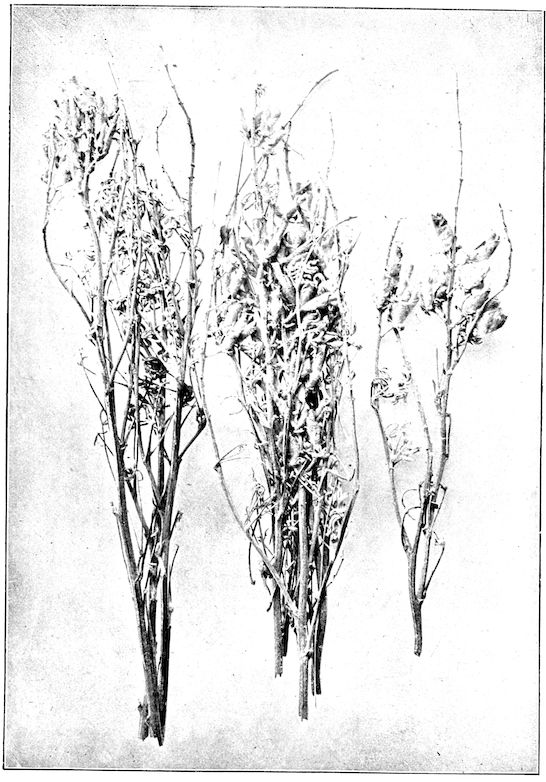

Fig. 3.—Pig suffering from osseous cachexia (fourth stage).

Such shocks would be of no importance to a healthy animal, but to one suffering from osseous cachexia, any violence, or even the slightest muscular effort may be followed by fracture of the gravest character, involving even the vertebral column. In cows the pelvis, femur, and tibia are most frequently injured.

In horses, particularly in riding horses, fractures are commonest in the region of the forearm, cannon bone, and anterior phalanges. So extremely fragile are the bones at this stage that the horse represented herewith broke twelve ribs at one time by simply falling on its side. It is interesting to note that such fractures are never accompanied by any extensive bleeding. They have little tendency to repair, no real callus formation occurs, and on post-mortem examination one often finds the ends unconnected by temporary callus, worn, and rounded by reciprocal friction.

At this stage but under other circumstances, the animals show great reluctance to rise, remaining down for twelve to twenty-four hours without shifting their position. If forced to get up, they stand as though fixed in one position, the respiration and circulation become rapid, and they soon grow tired and fall.

114. The fourth phase, or period of osteomalacia, i.e. softening of the bones, is also the last. It is rarely seen in large animals like horses and oxen, because accidents so often accompany the preceding stages and necessitate slaughter; but it is common in goats and pigs.

In this phase the bones become elastic, soft and depressible, yielding to the pressure of the operator’s fingers.

Fig. 4.—Deformity of the face in the horse shown in Fig. 2.

The flat bones are particularly liable to this change, which is common to domesticated animals. The bones of the head are the first to suffer; later those of the pelvis. The lower jaw becomes swollen, particularly about the centre of the branches which may attain three, four, or five times, their normal thickness.

The depression in the submaxillary space disappears. The upper jaw undergoes similar changes, becoming deformed and thickened until the cavities of the sinuses and the hollow appearance of the palate are lost, while the face is so changed that it cannot be recognised as that of a horse, goat, etc.

The molar teeth are almost buried, their tables alone being visible at the bottom of a depression, the edges of which rise above the neighbouring parts (pig).

Mastication is clearly impossible, the jaws appear paralysed, the muscles powerless, and only swallowing is possible, a fact which explains why life is only prolonged to this stage in animals which can be fed with a spoon or bottle (pigs and goats). The bones of the cranium, although greatly changed in texture, are always less deformed than those of the face.

The changes are such that it is often easy with a mere post-mortem knife to cut the head completely in two. Osseous tissue, properly so-called, has disappeared.

All the constituent tissues, with the exception of the skin and muscles, i.e., the bone, periosteum and aponeuroses, have the appearance and consistence on section of the fibro-lardaceous tissue seen in chronic inflammation.

Regarding the development of the disease in pigs, we may repeat what has just been said respecting the goat. Walking on the knees is often one of the first signs, fractures are somewhat rare, and the period of softening and deformity is always very noticeable.